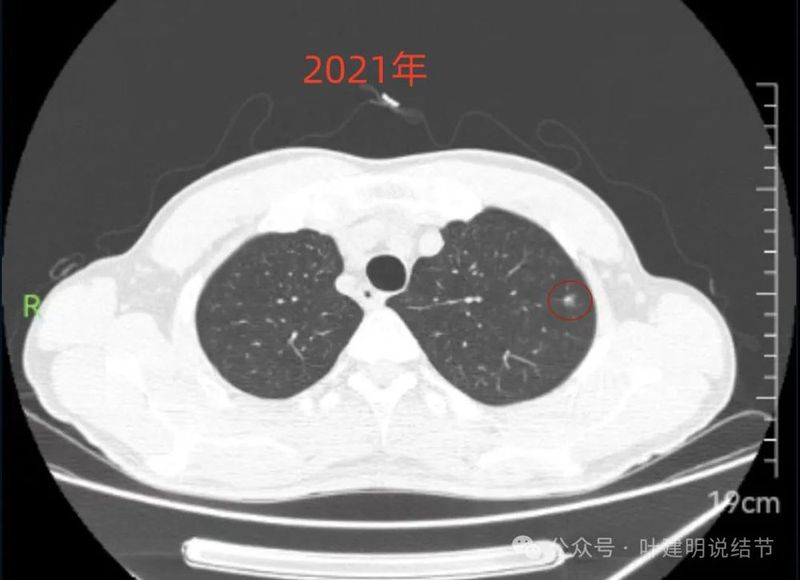

2021年6月右中叶病灶,较前无明显变化。

病灶上缘即偏实性,非圆形或类圆形。

边上有少许淡面模糊的磨玻璃成分。

轮廓欠清,瘤肺边界也不清晰。